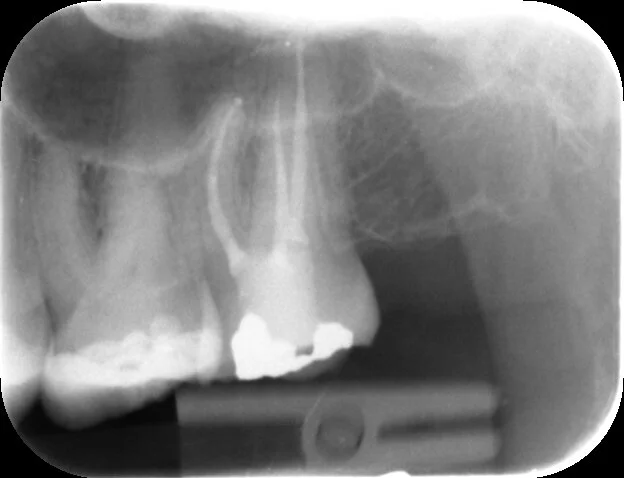

All canals are well obturated to length with a good apical-coronal seal